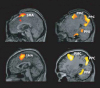

Так называемые люди-«овощи» с полным отсутствием реакции на внешние стимулы способны осознавать себя, мыслить, сотрудничать с врачами. 23-летняя пациентка-«овощ» смогла по просьбе врачей представить заданную последовательность действий, при этом магнитные томограммы ее мозга не отличались от томограмм здоровых добровольцев.